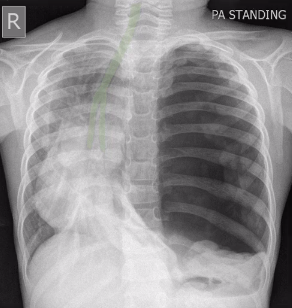

whats wrong here?

whats up here?

hilum enlarged